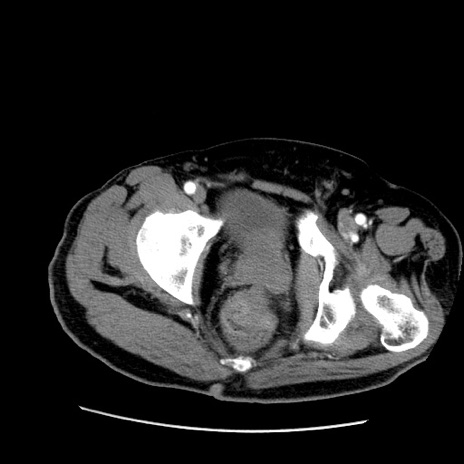

症例22(横断像)

【症例】50歳代男性

【主訴】腹痛

【現病歴】AVMからの被殻出血のため回復期リハ病棟入院中。 本日午後3時頃急に下腹部痛が出現した。

【既往歴】AVM、被殻出血、虫垂炎、高血圧

【身体所見】意識晴明、左半身不全麻痺、会話の理解は良好、36.5°C、腹部:膨隆、全体に板状硬、下腹部正中に圧痛点あり、反跳痛-、筋性防御不明、右下腹部にope scar

【データ】WBC 9400、CRP 0.06